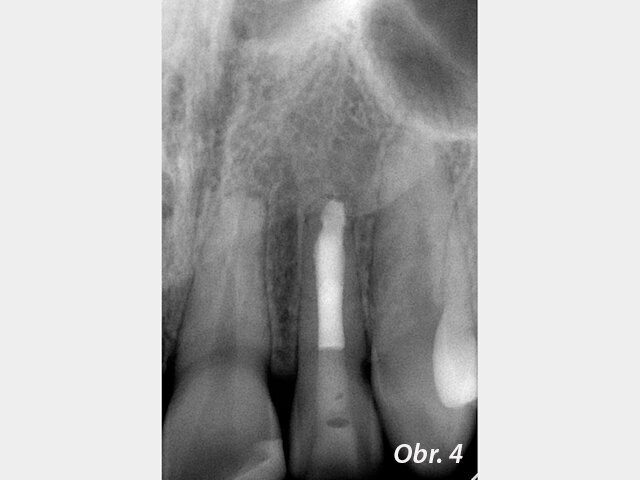

Zánětlivé změny v periapikálních tkáních a současně schopnost hypochloridu rozpouštět měkké tkáně mohou vést ke vzniku prázdného prostoru periapikálně. Pravděpodobnost přetlačení MTA do periapikálního prostoru je pak velká. Vzhledem k biokompatibilitě tohoto materiálu se nejedná o komplikaci, která by ohrožovala výsledek ošetření (obr. 1–4), není však žádoucí. Pokud periapikální tkáně nevytvářejí přirozenou bariéru, která přetlačení MTA brání, je možné takovouto bariéru vytvořit z kolagenu.